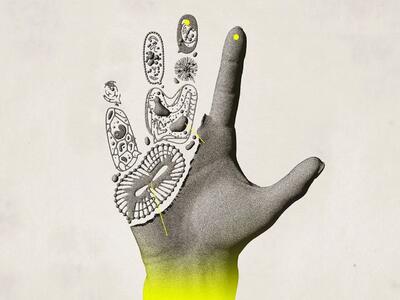

بافت بدن

پروتئین بعد از هضم شدن به واحدهای سازندهی خود یعنی اسید آمینه تجزیه میشود. اسید آمینه به عملکرد و رشد بافتهای بدن کمک کرده و از سلامت عضلات، استخوانها، پوست، مو و ناخن محافظت میکند

فتق نافی چیست؟

رکنا: فتق نافی یک وضعیت شایع است که به بیرون زدگی بافت یا اعضای داخلی بدن از طریق ناحیه ضعیف دیواره شکم اطراف ناف گفته میشود. این مشکل معمولاً در نوزادان و کودکان دیده میشود، اما در بزرگسالان نیز ممکن است رخ دهد و در بسیاری از موارد نیاز به درمان جراحی پیدا میکند.

بیماریهای خودایمنی زمانی ایجاد میشوند که سیستم ایمنی بدن که قرار است با مهاجمان بیرونی مبارزه کند، به اشتباه به بافتهای سالم خود بدن حملهور میشود. این حملات اشتباهی میتوانند التهاب، آسیب و اختلال در عملکرد انواع ارگانها و سیستمها ایجاد کنند.